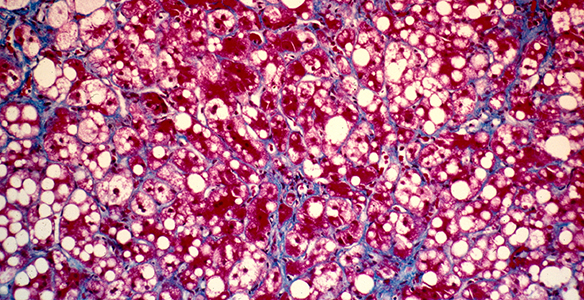

Die Leber ist die Entgiftungszentrale und größte Drüse des Menschen. Sie ist zentrales Stoffwechsel- sowie Speicherorgan und für das Immunsystem von übergeordneter Bedeutung. Die Behandlung von Lebererkrankungen bzw. Lebertumoren ist dementsprechend komplex und erfordert eine enge, fächerübergreifende Zusammenarbeit. Die Innsbrucker Univ.-Kliniken weisen dazu eine hohe Expertise auf diesem Gebiet auf. Im Leber Centrum Innsbruck (LCI) werden modernste Therapien, welche auf den einzelnen Patienten maßgeschneidert sind, angeboten. Unter anderem umfassen diese:

- Leberresektion: Am Leber Centrum Innsbruck wird das gesamte Spektrum der operativen Entfernung von Lebertumoren bzw. Lebermetastasen angeboten. Die chirurgische Therapie wird vorab in gemeinsamen Tumorkonferenzen mit allen anderen beteiligten Disziplinen (z.B. Onkologie, Gastroenterologie, Radiologie, Radiotherapie, Pathologie, Anästhesie) individuell auf jeden Patienten abgestimmt, um ein bestmögliches Resultat zu erzielen. Eine besondere Bedeutung kommt hierbei der Planung von mehrstufigen Therapien zu, bei denen z.B. mehrzeitige chirurgische Eingriffe und/oder Radiofrequenzablationen mit systemischen Therapien (Chemotherapie) kombiniert werden für ein optimales Tumoransprechen. ->Univ.-Klinik für Visceral-, Transplantations- und Thoraxchirurgie.